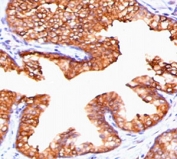

IHC staining of FFPE human prostate carcinoma with TMEPAI antibody (clone PMEPA1/2697). HIER: boil tissue sections in pH 9 10mM Tris with 1mM EDTA for 10-20 min and allow to cool before testing.